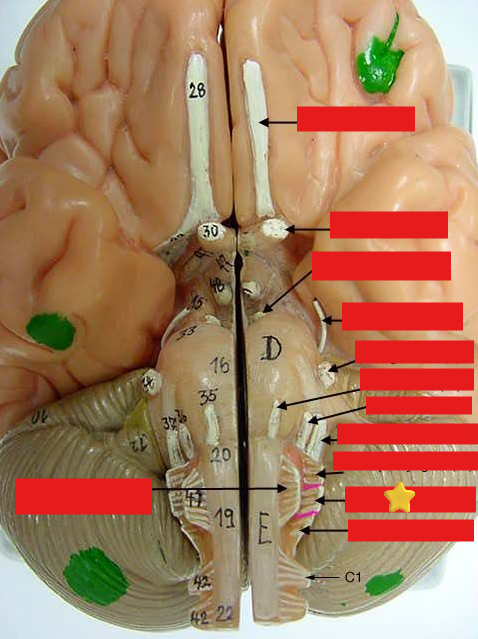

cranial nerves

12 Terms

1

olfactory

2

optic

3

oculomotor

4

trochlear

5

trigeminal

6

abucens

New cards

7

facial

8

vestibulocochlear

New cards

9

glossopharyngeal

New cards

10

vagus

New cards

11

accessory

New cards

12

hypoglossal

New cards